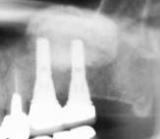

サイナスリフト | |||||||||||

| 近年のインプラント治療の進歩はめざましく、以前ではインプラント植立が不可能な場所にも再生療法を応用してインプラントの植立が可能な時代になりました。インプラントをするために、上の奥歯の骨が無い時に行う再生療法です。(POIワイドタイプインプラント使用) | ![]() |

【術前】 |

【術後】 |